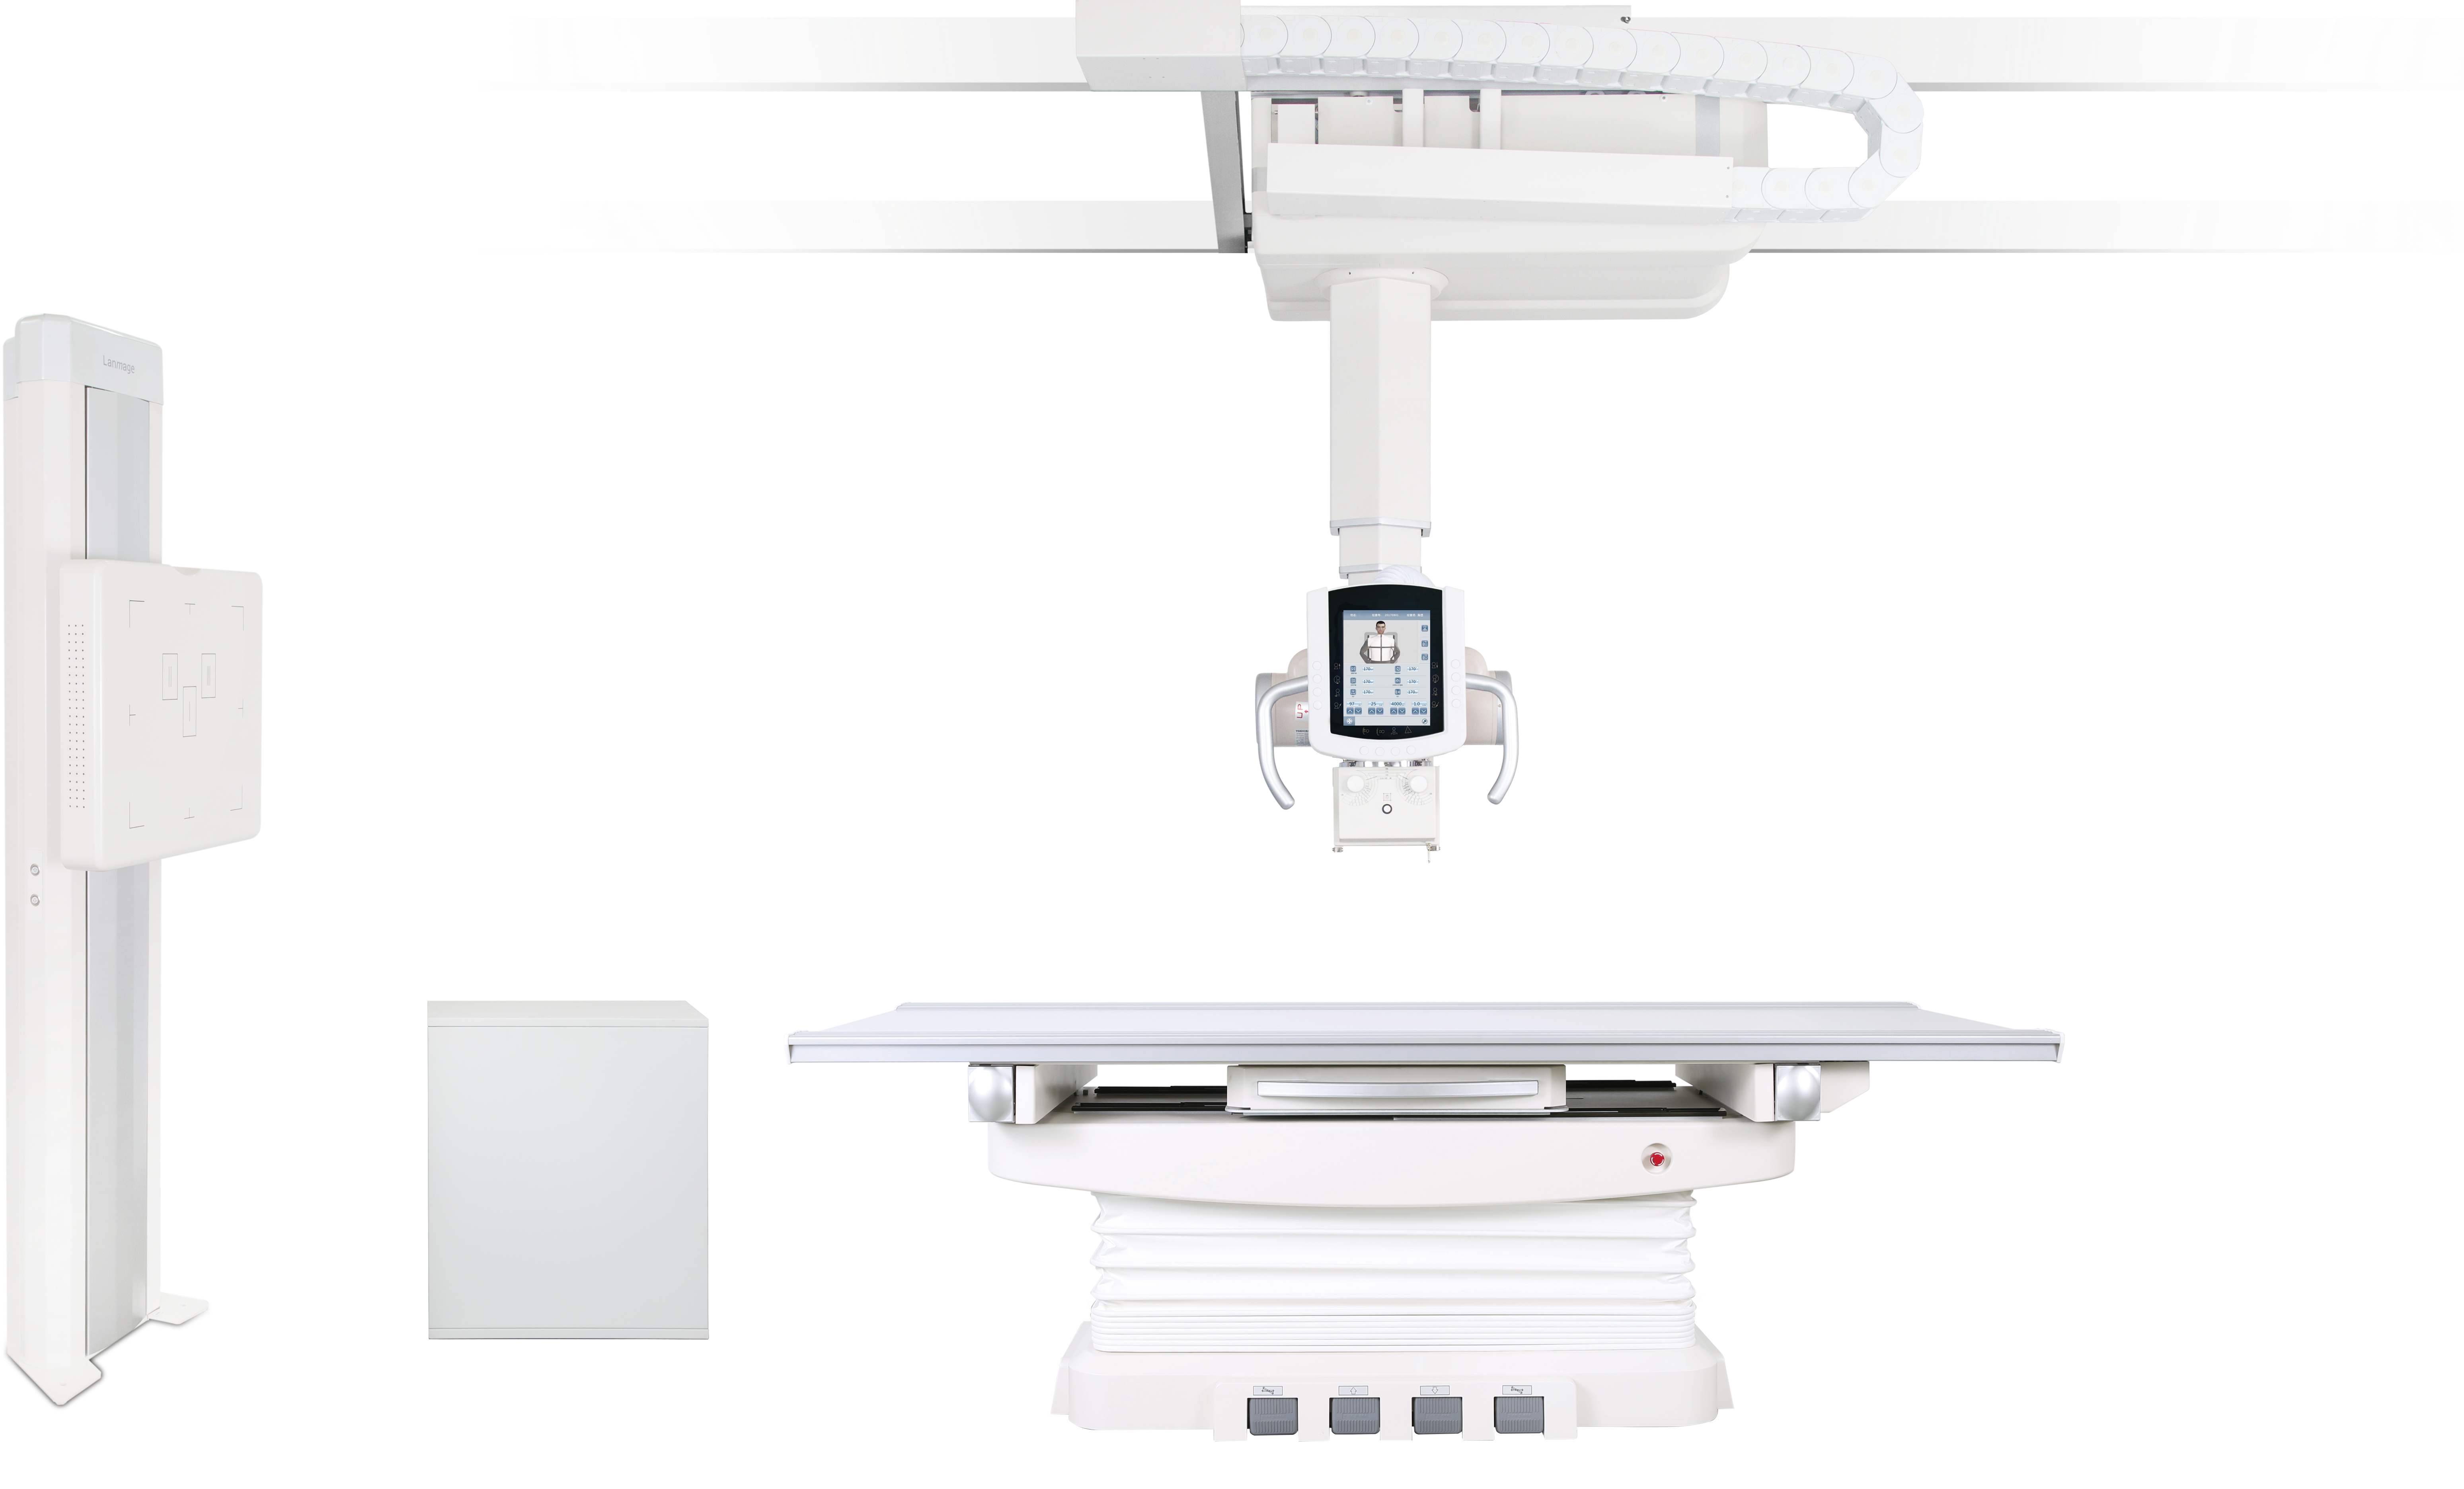

Lanmage propose des systèmes d’imagerie médicale avancés, combinant haute performance et technologies modernes pour offrir des images précises et un diagnostic fiable dans divers domaines de la radiologie.